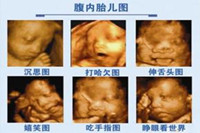

隨著祖國醫(yī)學(xué)技術(shù)的不斷發(fā)展,目前來說最先進(jìn)的彩色超聲設(shè)備,屬四維彩超莫屬。有很多孕媽咪不知道四維彩超的準(zhǔn)確時(shí)間,更不知道四維彩超的真正意義。其實(shí),四維彩超在懷孕...

四維彩超,不管是看胎兒在腹中的發(fā)育情況,還是看胎兒性別,都讓人深信不疑。那么,四維彩超上面真的有男女暗示嗎?四維彩超又是怎么看男女的呢?...